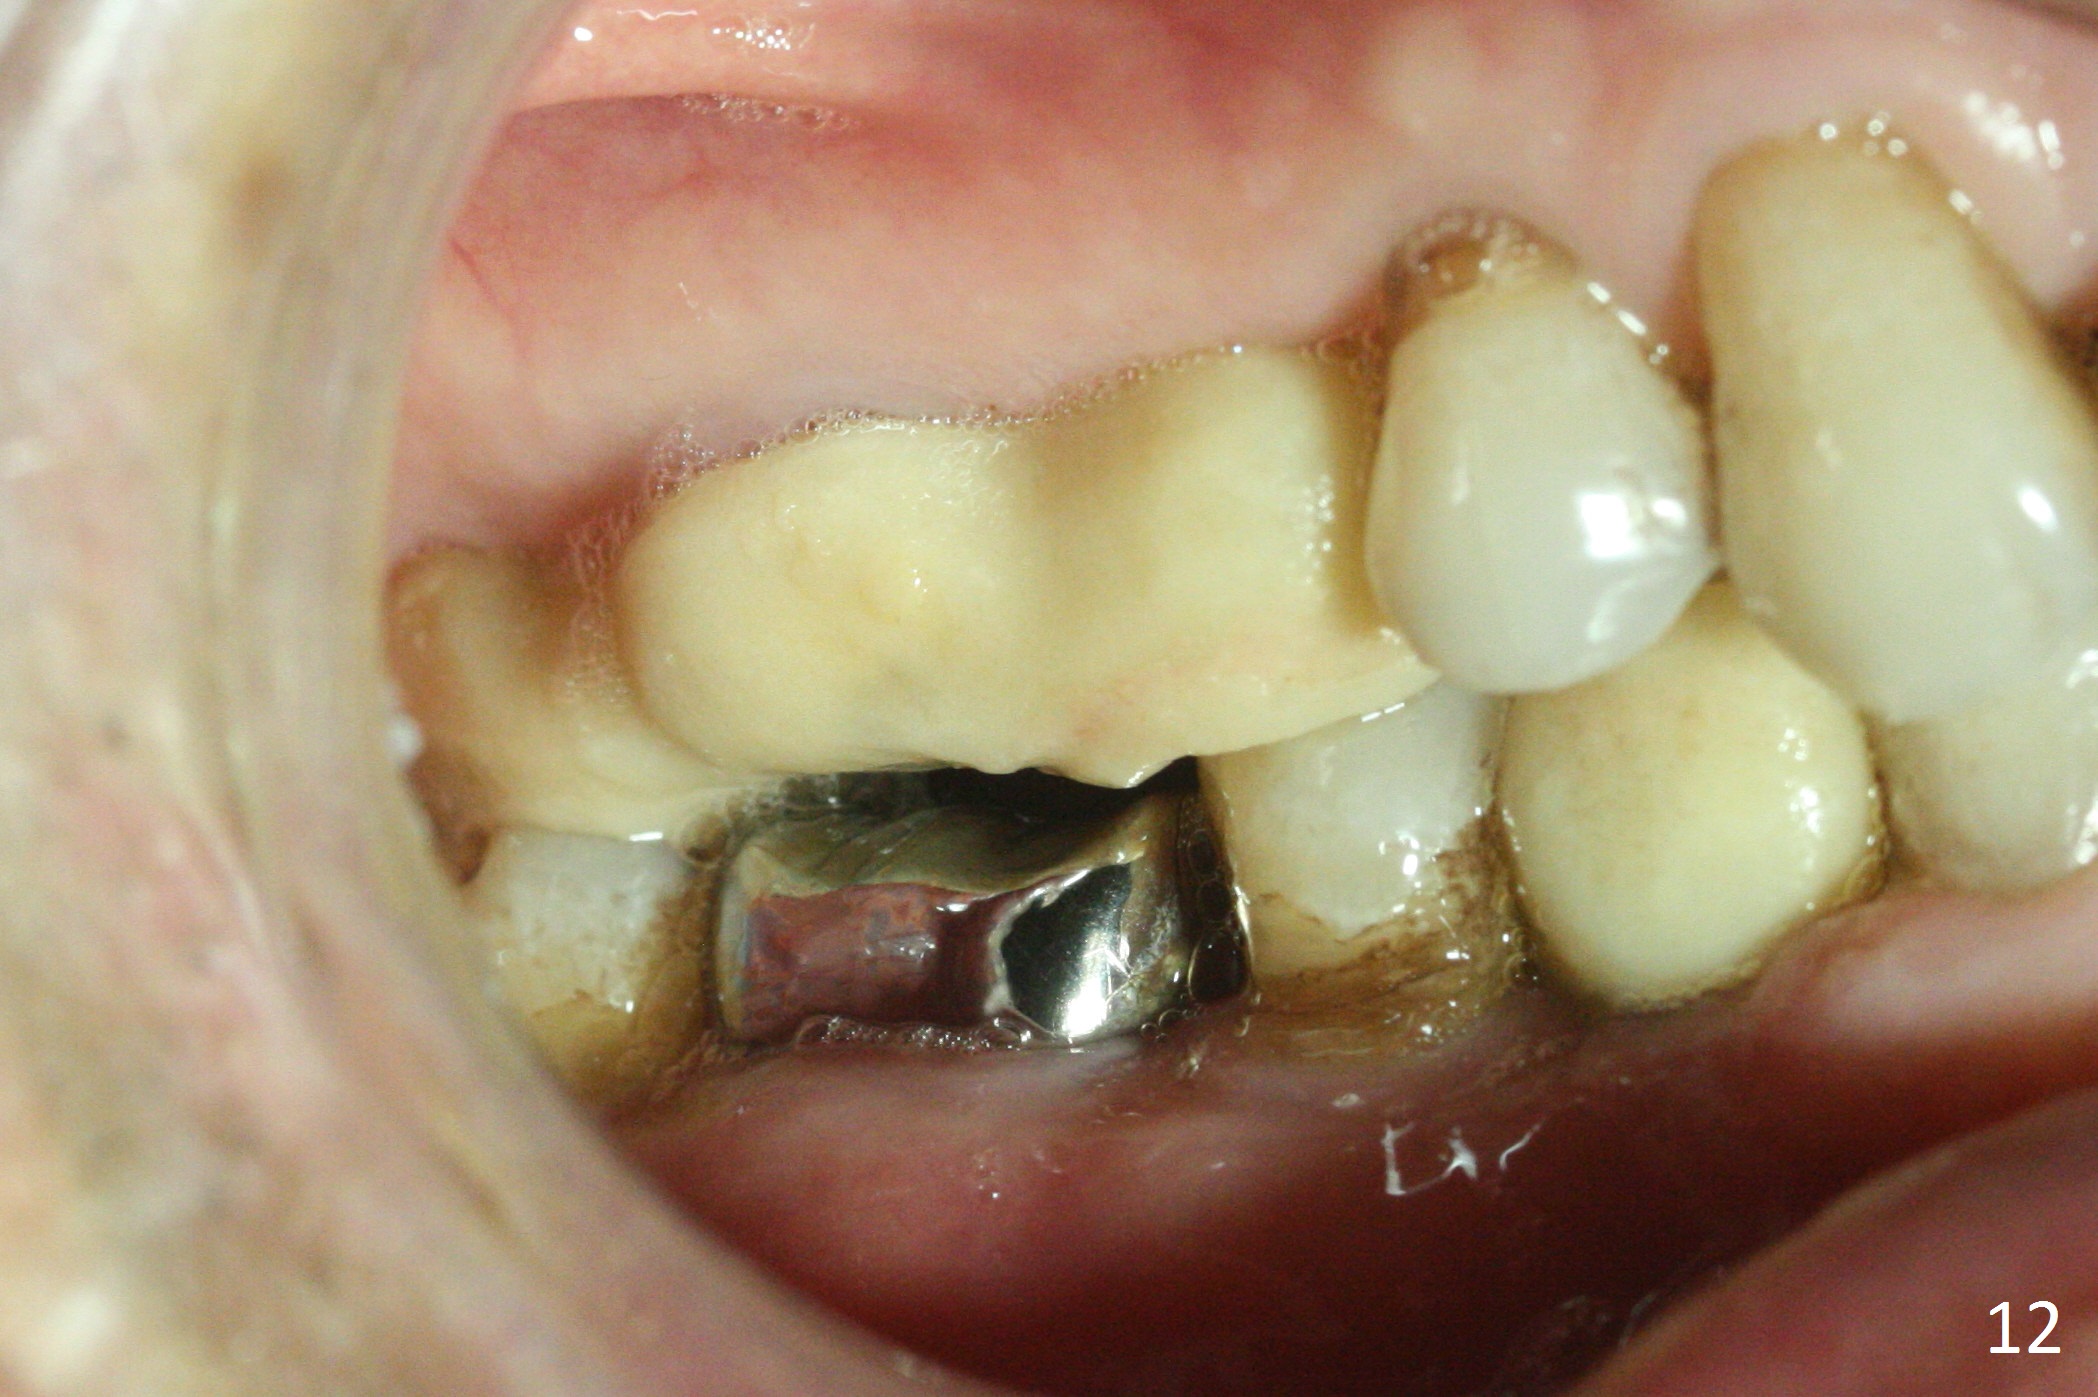

In fact the upper provisional has been extended to cover #2-4 three months postop. When the patient returns again, it is approximately 4 months postop for #2 and 4 (Fig.9,10) and 3 months for #28. Reline or make the provisional so that the teeth #5 and 29 will be intruded (Fig.11 preop pan for comparision). The tooth #30 appears to have been intruded for the past 4 months. The provisional at #3 is short so that the tooth #30 may be able to erupt (Fig.12).